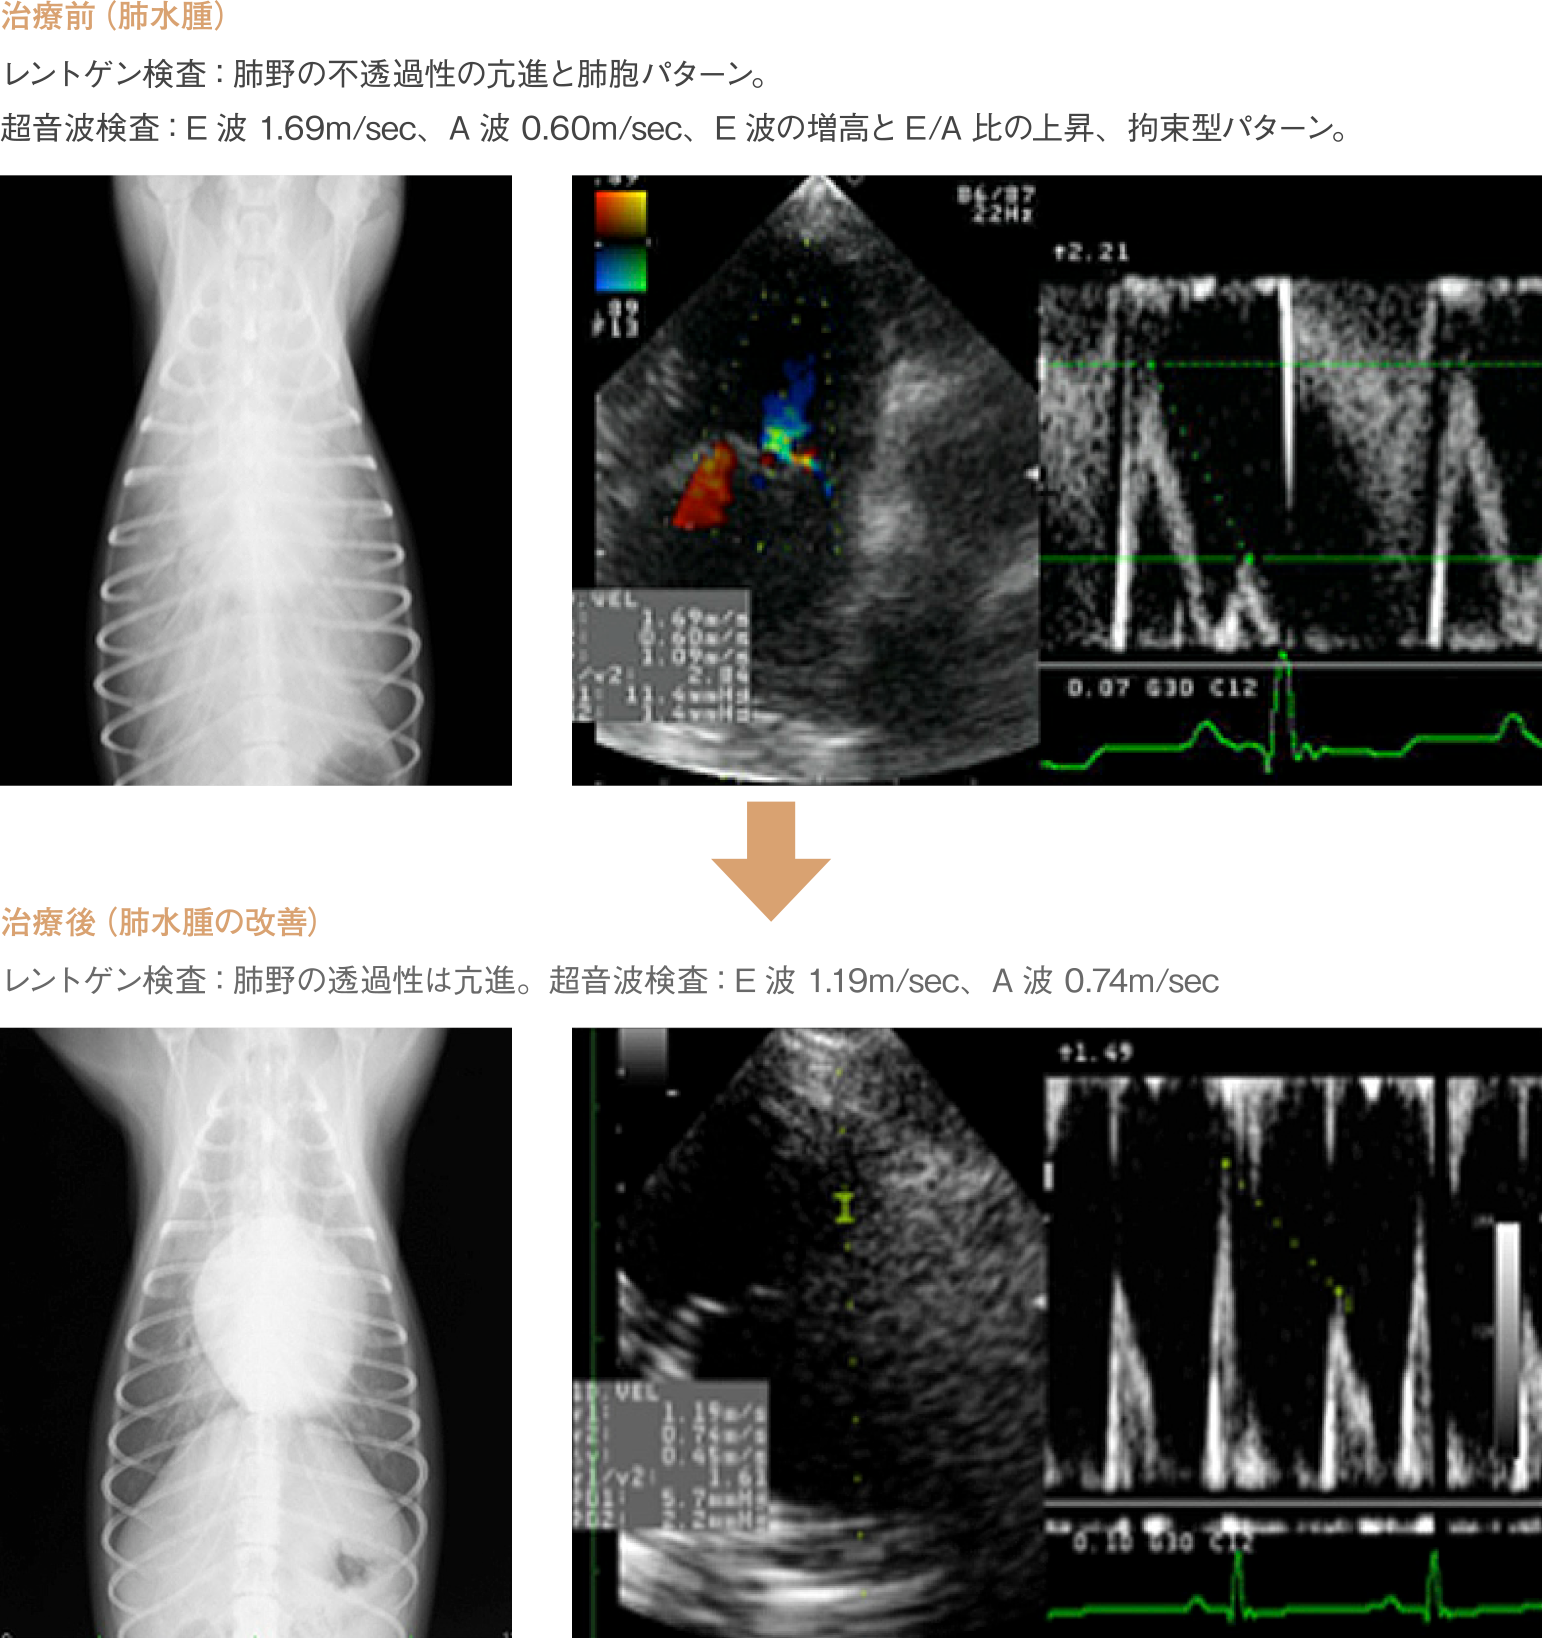

超音波検査

心臓の超音波検査をすることで、心臓の弁の動きや心臓の各部屋の大きさ、筋肉の厚さなど心臓の内部まで詳細に把握する事が可能です。また、心臓内を流れる血液の早さを測る事で、心臓の機能の厳密なモニターが可能です。心臓の何処がどのように大きくなっているのか、血液の流れはどうなのか、はっきりと把握することが、適した治療につながります。

血液の流れる向きを色で示し、逆流やジェットを明らかにします。

流速の計測

弁を流れる血液の早さを測り、血流の異常を探ります。

僧帽弁閉鎖不全症は心臓の血流を調整する僧帽弁という弁の機能が低下し、 本来一方通行である血液の流れに逆流がおきる病気です。中年齢以降の犬に多くみられます。症状としては発咳や運動性の低下、進行すると呼吸困難やチアノーゼがみられます。

さらに重症化すると肺水腫といって肺に水がたまり命に関わる事もあります。

聴診では心雑音が聴取され、雑音は程度により6段階に分類されます。また、心音の聞こえ方により胸水や心嚢水の存在を疑う事や、肺音の異常から肺水腫を疑う事も可能です。この他、呼吸様式や回数、舌などの粘膜の色は重要な情報となります。この病気が疑われた場合、胸部X 線検査や超音波検査、さらに心電図検査や血圧の測定を行い、上記のACVIM分類に則って評価します。

治療は検査によって把握した分類に応じて行います。初期の場合には低ナトリウムを主とした食事療法での管理が可能ですが、ステージが進行すると様々な内服薬が必要となります。心臓の状況は刻一刻と変化するため、定期的なチェックと状況に合わせた内服薬の調整が必要です。それぞれの症例で病態は全く異なるため、まずは当院獣医師にご相談下さい。